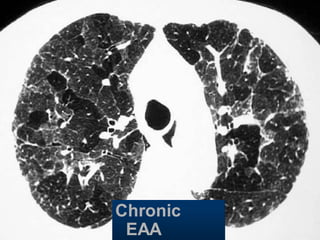

Bronchiolitis

obliterans

Early Sarcoidosis

Chronic

EAA

Hypersensitivity pneumonitis

Extr. Allerg. Alveolitis (EAA) HRCT

Morphology

chronic: fibrosis

Intra- / interlobular septal thickening

Irregular interfaces

Traction bronchiectasis

acute - subacute

acinar (centrilobular) unsharp densities

ground glass (patchy - diffuse)